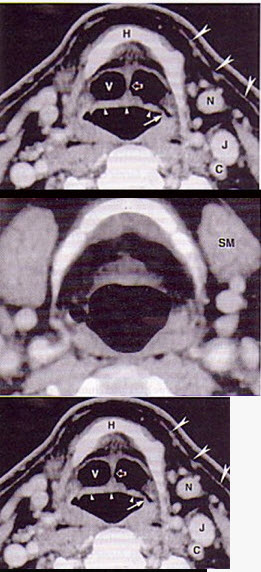

男,55岁,声嘶6年,有长期吸烟史。检查:无呼吸困难。喉镜检查:声带慢性充血,可见右侧声带可见菜花样新生物,右侧声带活动固定,喉部CT检查如下图: